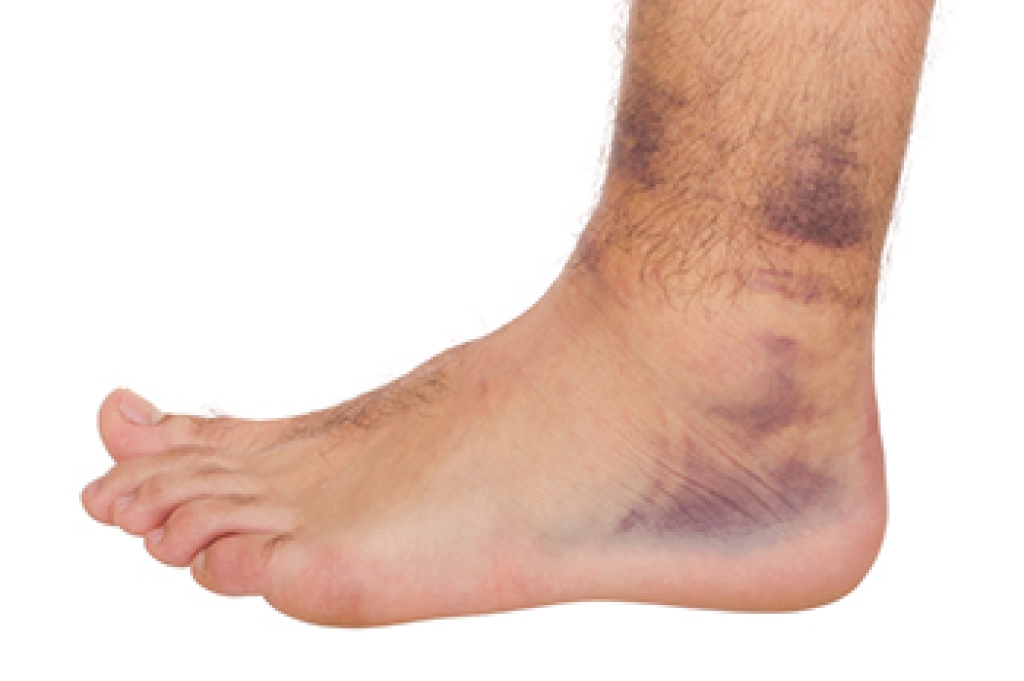

- Injury (from stress fractures, broken toe, foot, ankle, Achilles tendon ruptures, and sprains)

To figure out the cause of foot pain, podiatrists utilize several different methods. This can range from simple visual inspections and sensation tests to X-rays and MRI scans. Prior medical history, family medical history, and any recent physical traumatic events will all be taken into consideration for a proper diagnosis.

Treatment depends upon the cause of the foot pain. Whether it is resting, staying off the foot, or having surgery; podiatrists have a number of treatment options available for foot pain.